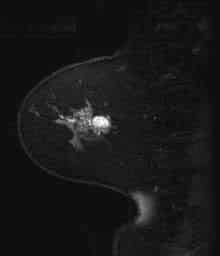

Imagenes de la mama en RM